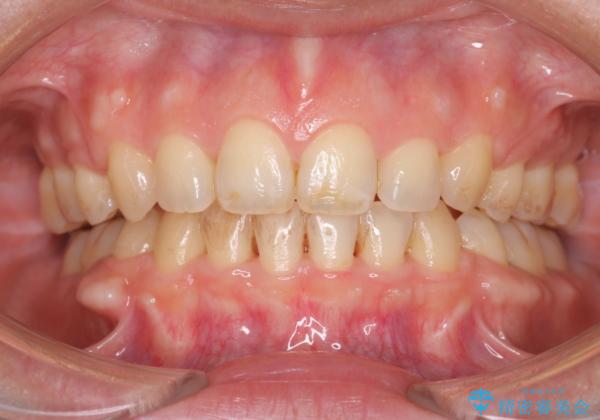

- メンテナンスの際に歯のステインが気になるということで今回はエアフローの機械を使用したクリーニングを行いました。

ステインが付着したままだと歯の表面がざらつき、普段のブラッシング時などに汚れが落ちにくくなります。定期的なメンテナンスの際にPMTC、エアフローを取り入れることをおすすめしております。